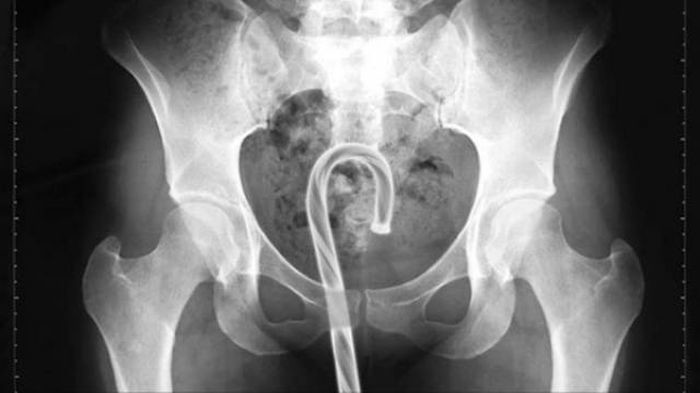

Предметы, которые не очень хочется видеть внутри себя

Под рентгеновскими лучами порой видны не только внутренние органы и кости, но и инородные тела, попавшие в организм

Истории попадания этих предметов в организм могут быть самыми невероятными и запутанными, но больше всего медиков интересует процесс их извлечения, впрочем, в этом заинтересованы и сами пациенты, допустившие нечто подобное со своим телом.